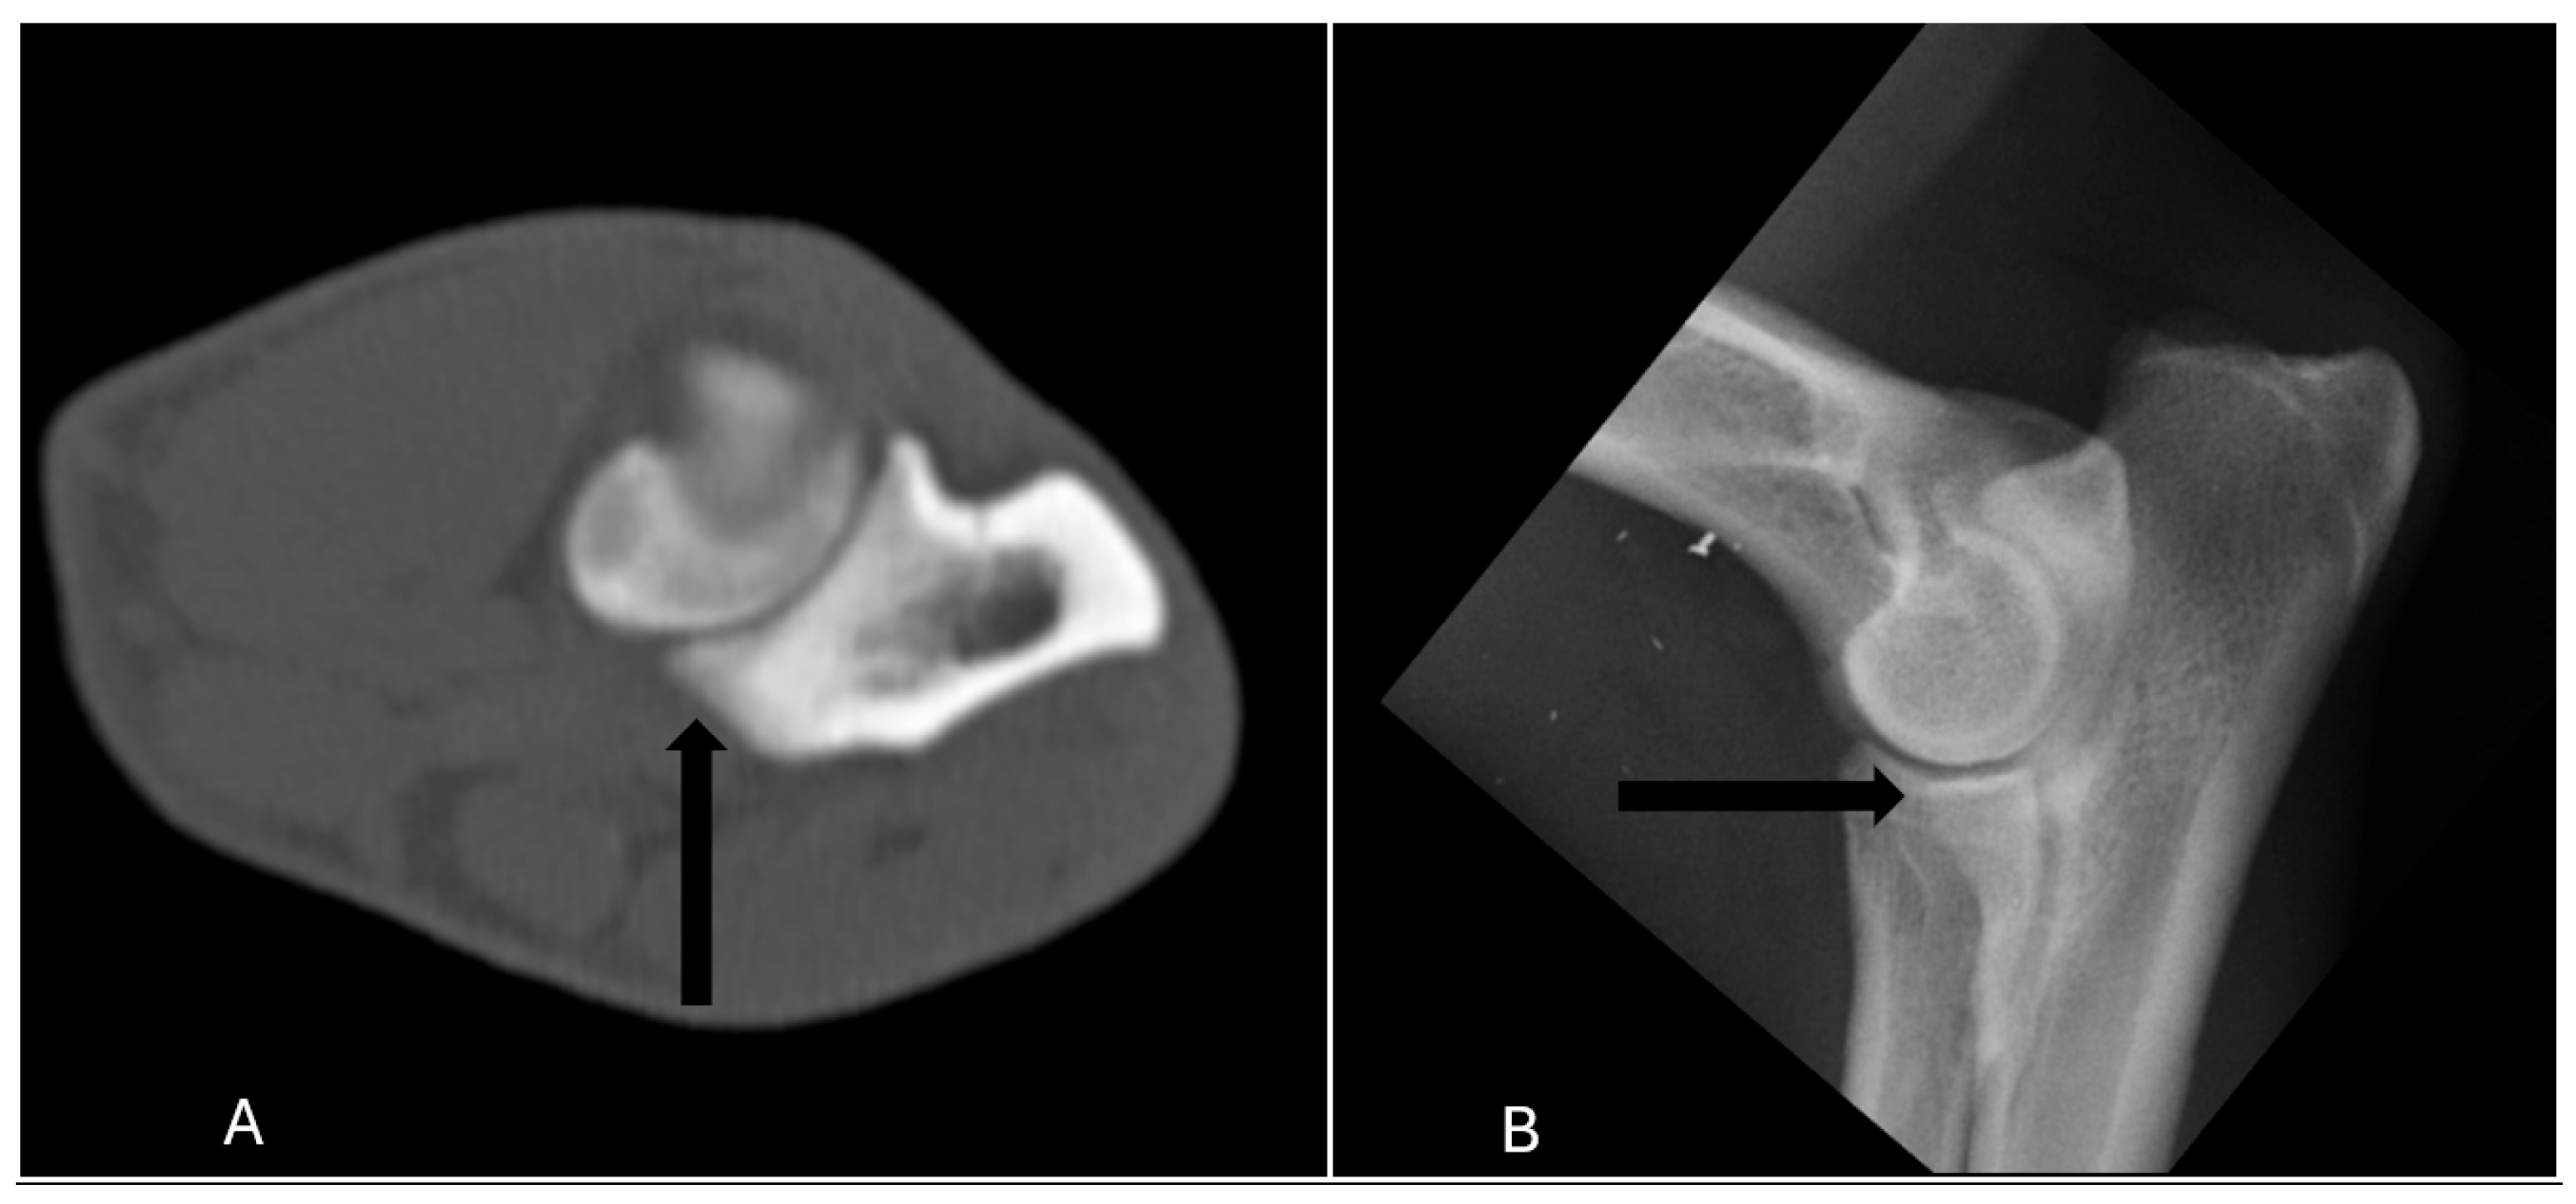

In terms of diagnostic accuracy, the comparison between radiographic and CT assessments revealed that radiography had a sensitivity of 65% (17/26) and a specificity of 93% (369/398) (Table 1). Specifically, nine elbow joints (9/26) were false negatives, meaning that MCD was detected in these joints only by CT and reported normal in radiography (Figure 1). Conversely, 29 joints (7%) were classified as false positives, indicating that radiography indicated the presence of MCD when in CT no abnormalities were detect. (Figure 2). The positive predictive value was 37% (17/46), while the negative predictive value was 98% (369/378) (Table 1).

Figure 1. The lateral radiograph and transverse image of the right elbow of a 24 months old German shepherd which was classified as false negative, meaning that medial coronoid process was scored abnormal with a fissure (arrow) only in CT (A), and reported normal in radiography (B).